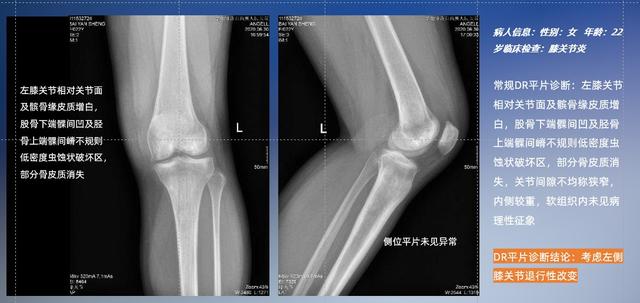

以膝关节疾病检查为例,膝关节在解剖学意义上是一种较为复杂的最大关节,由胫骨上端、股骨下端及髌骨组成。在股骨与胫骨的关节面之间存在两块半月板,分别处于内侧、外侧。膝关节的运动主要为伸、屈,在半屈位时可进行小幅度的旋外、旋内运动。随着现代人们体育生活以及肥胖的增加,膝关节疾病出现高发趋势,特别是关节磨损、膝关节炎与骨关节炎等关节退行性改变,长时间的内翻负荷会造成内侧关节软骨、骨性关节面的磨损。目前针对此类疾病的检查主要为平片下的负重位检查、CT检查以及MRI检查,相较于非负重位检查,负重位检查能更加真实反映膝关节结构中胫骨、股骨、髌骨实际对位关系和关节面的形态特征及关节间隙大小,对膝关节骨关节病诊断准确率高。

普通平片扫描与WR-3D扫描前后诊断结果对比

在负重位状态下,数字化X线三维扫描与重建,能够更好的呈现受检者关节受力改变的状态。ty8天游平台登录科技创新的WR-3D动态三维影像重建系统,通过数字化X线摄影完成三维扫描并重建三维影像信息,包括断层图像重建、MPR多平面重建、MIP重建以及VR体绘制。其扫描时间短,剂量相较于CT设备大幅缩减,同时成本更低,在临床诊断以及医疗方案制定中具有极大的价值意义。而相较于普通平片下的负重位扫描,负重位动态三维影像重建技术能够避免二维状态下的组织结构重叠、密度分辨率不足、组织解剖结构难以分辨等问题。WR-3D支持多角度的三维观察,能全面的呈现被检查部位在多个角度下的三维影像信息,极大的降低了二维负重位检查带来的漏诊率。